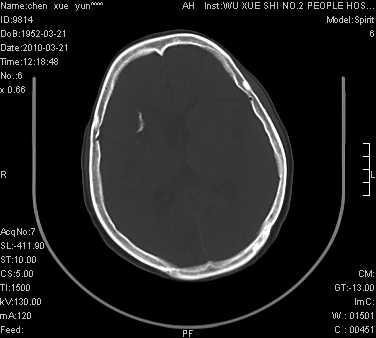

性别:不详;年龄:58岁;病史:不详。

ct表现:1、右侧额颞叶深部不规则钙化密度团块,呈弯曲条带状,占位效应不明显,考虑少枝胶质细胞瘤可能性大于血管瘤。2、右枕叶大片不规则低密度影,密度近似于脑脊液,右侧侧脑室后角及三角区扩张,考虑为陈旧性脑梗塞。

讨论:1、这个病灶的钙化有点像脑回样钙化,因此我最初考虑颅面血管瘤病(sturge-weber综合征),但是查阅了我们网站上的几个颅面血管瘤病病例,钙化均位于脑实质表面,沿脑回分布,而这例病灶位置较深,因此可以否定“颅面血管瘤病”这个诊断。

2、卜一会员曾经说过:少枝胶质细胞瘤的典型征象为弯曲条带状钙化,可作为定性的可靠征象(http://www.radida.com/news_view.asp?id=5150)

3、血管瘤也可以出现弯曲条带状钙化,但血管瘤多数出现“负占位”效应,即病灶周围的脑室、脑池及脑沟不是受压变窄,而是局限性的增宽。